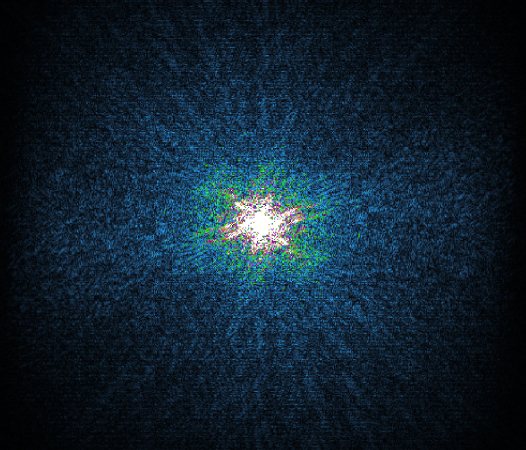

Philips Compressed SENSE

The Compressed SENSE reconstruction then uses iterative, knowledge-based algorithms to fill in the empty lines in k-space (bottom left). This removes the artifacts while keeping the final image fully consistent with the acquired data (bottom right). *Compared to Philips MR exams without Compressed SENSE